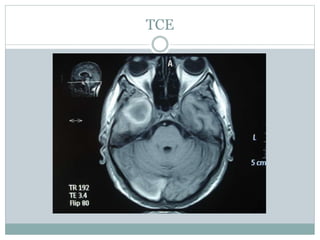

TCE

TCE –lesion temporal